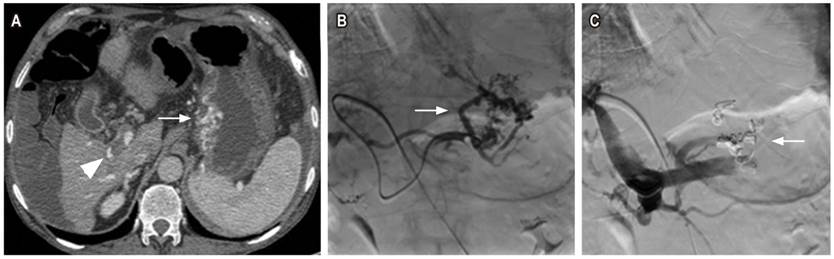

Cuarto caso

Paciente femenina de 69 años con antecedente de cirrosis hepática de origen alcohólico, con puntaje Child Pugh C, quien consulta por un sangrado digestivo alto de difícil manejo endoscópico de origen variceal esofágico y gástrico. El paciente ameritó protección de la vía aérea debido al riesgo de broncoaspiración, múltiples transfusiones y soporte vasopresor. Se considera la realización de una embolización por vía transparietohepática. En la tomografía de abdomen contrastada se observan várices tortuosas adyacentes a la curvatura menor del estómago (Figura 4A). Se realiza una venografía selectiva de acceso retrógrado portal opacificando várices tortuosas en la curvatura menor gástrica (Figura 4B) y una embolización con coils y Gelfoam® (Figura 4C) ocluyendo el flujo en várices. El procedimiento se realizó sin complicaciones y se pudo controlar el sangrado de la paciente.